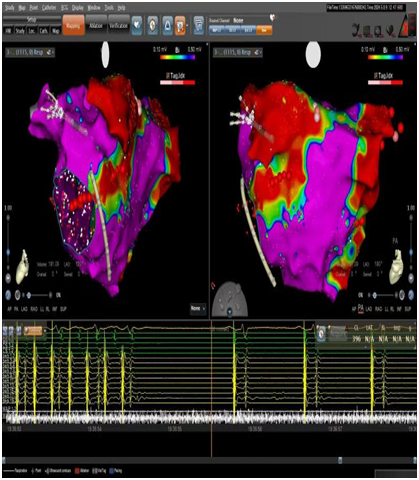

图片

▲房扑终止

手术中通过电生理检查

找到“罪魁祸首”——

沈先生的心外膜Marshall静脉

参与并维持着心房颤动、心房扑动反复发作

冯振勤主任医师、赵波副主任医师

凭借丰富的临床经验和娴熟的手法

先完成

心脏Marshall静脉的无水乙醇化学消融

再完成

经导管心房肺静脉心内膜联合射频消融

进行彻底的病灶阻滞

每分钟130次的心房扑动节律终止

心电为每分钟70次的窦性心律